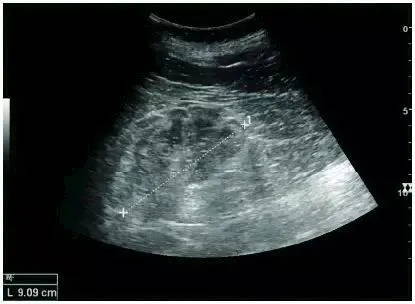

Ultrasound is an important method for diagnosing chronic kidney disease and judging prognosis. Whether it is glomerulosclerosis, tubular atrophy, interstitial fibrosis, or inflammation, echogenic cortical enhancement is seen on ultrasound imaging. Normal kidney echoes are similar to those of the liver or spleen. In addition, renal atrophy and cortical thinning are common, especially as the disease progresses. However, kidney size correlates with height, and patients with short stature have smaller kidneys; therefore, kidney size should not be used as the sole criterion.

Chronic kidney disease due to glomerulonephritis: thinning of the cortex and increased echogenicity. +, dotted line: kidney length

Nephrotic syndrome: echogenic demarcation of renal cortex and medulla

Chronic pyelonephritis: renal atrophy, focal cortical thinning. +, dotted line: kidney length